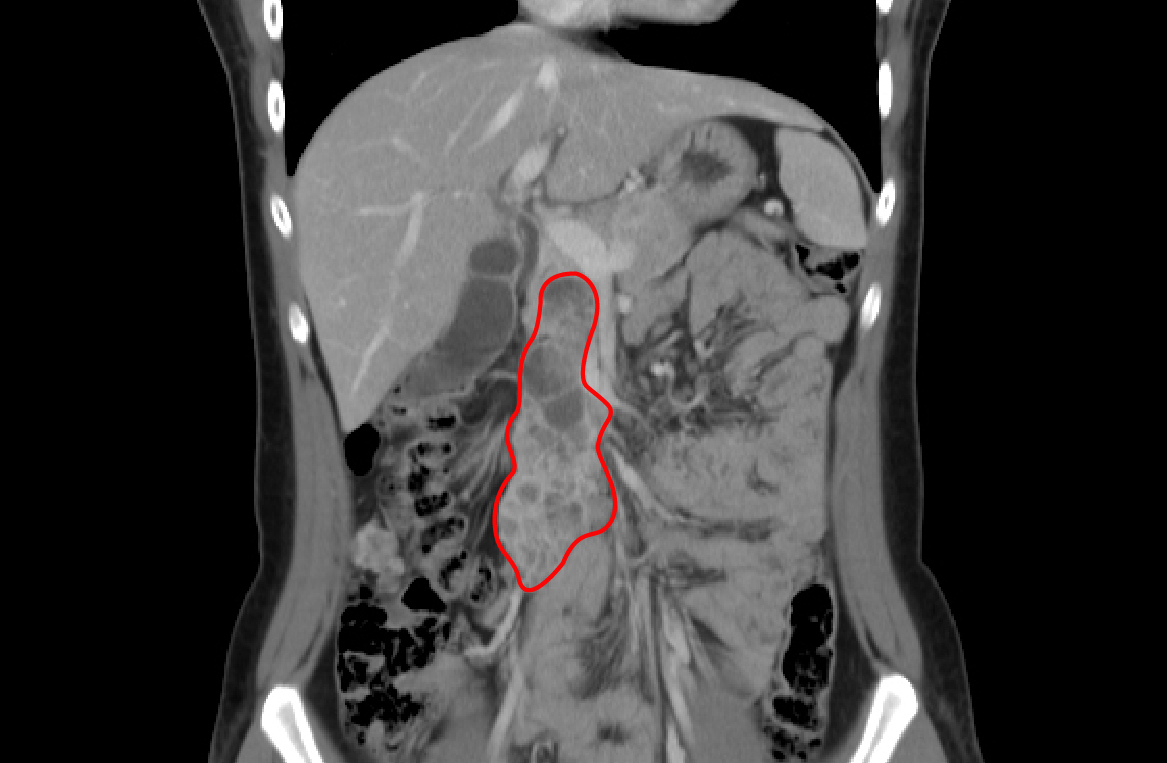

图中红圈内为肿瘤大致范围

单从疾病诊断上,梓婷具有手术指征,但肿瘤侵袭范围过广,“肠系膜静脉主干及根部受到肿瘤包裹,属于外科手术的禁忌症。”多学科联合会诊上,胃肠外科主任李元新说。肠系膜静脉是从门静脉延续下来的,主干切除若不能重建,整个小肠会因失去血运而丧失,术后患者只能全肠外营养,靠静脉营养存活。